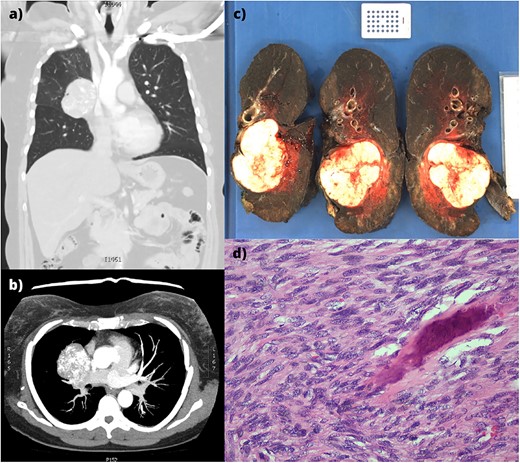

(a,b) CT imaging showing a large right hilar mass with compression of right main bronchus and superior vena cava. (c) Macroscopic appearance of the right lung containing the tumour and adjacent mediastinal structures. (d) Histopathology of the metastatic osteosarcoma, demonstrating atypical spindle cell morphology.

Histologically, the solitary tumour was well-circumscribed and un-encapsulated with atypical spindle cells in intersecting fascicles (Fig. 1d). Hyperchromasia, pleomorphism, nuclear atypia, and high mitotic indices were demonstrated. Osteoid with calcification was present, confirming osteosarcoma. The bronchovascular margin and lymph nodes were not involved.